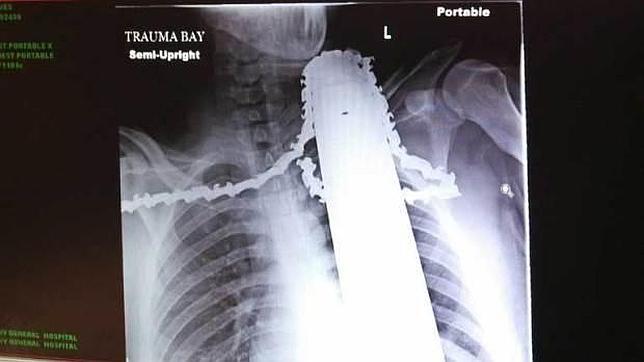

James Valentine, un podador de árboles de apenas 21 años, resultó gravemente herido el pasado lunes cuando, mientras cortaba varias ramas de un tronco en EE.UU., perdió el control de la motosierra que manejaba y se clavó su hoja en el cuello, según ha ... informado el « Pittsburg Post-Gazette » en su versión en línea. No obstante, y a pesar del accidente, el joven se encuentra fuera de peligro tras la intervención de los médicos.

Al parecer, el trágico suceso acaeció mientras James se encontraba subido a un árbol de varios metros de altura en el condado de Ross (EE.UU.). Cuando le quedaba poco para terminar el trabajo, el joven deicidio subir la motosierra que estaba manejando por encima de su cabeza para podar la parte más elevada del tronco. En ese momento, el instrumento se descontroló violentamente y terminó incrustándose varios centímetros en el cuello y el hombro del norteamericano.

Con un insufrible dolor recorriéndole todo el cuerpo, James no supo qué hacer. Por suerte, un compañero de trabajo vio la situación y bajó a la víctima del árbol. A los pocos minutos, una ambulancia llegó al lugar del accidente y logró, tras mucho esfuerzo y asombro, estabilizar a la víctima, aún con la hoja de la motosierra en el cuello. «Si se la hubiéramos quitado se hubiera producido una hemorragia masiva», explica uno de los médicos que le atendieron.

Finalmente, James fue trasladado al Hospital General de Allegheny , donde fue operado con éxito. Los médicos, por su parte, no podían creer que la motosierra no le hubiese tocado la arteria carótida, algo que le hubiese provocado la muerte. «Fue sólo un accidente. Podría pasarle a cualquiera con este trabajo. La motosierra se volvió hacia mí y se quedó atascada en mi cuello, pero (…) yo soy trepador de árboles, y eso es lo que voy a seguir haciendo cuando me recupere», explicó la víctima.